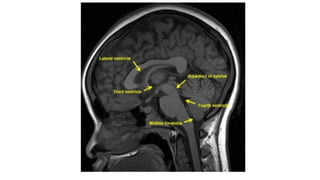

THE VENTRICLES

Ventricles

• Lateral ventricle

• Frontal horn

• Occipital horn

• Temporal horn

• Third ventricle

• Fourth ventricle

• Central canal

Foramen monoro

Aqueduct of Silvius

Interventricular foramina

(or foramina of monro)

The lateral ventricle

The frontal horn

The

occipital

horn

The temporal horn

The 3rd ventricle

The 4th ventricle

Foramen Luschka and Magendie